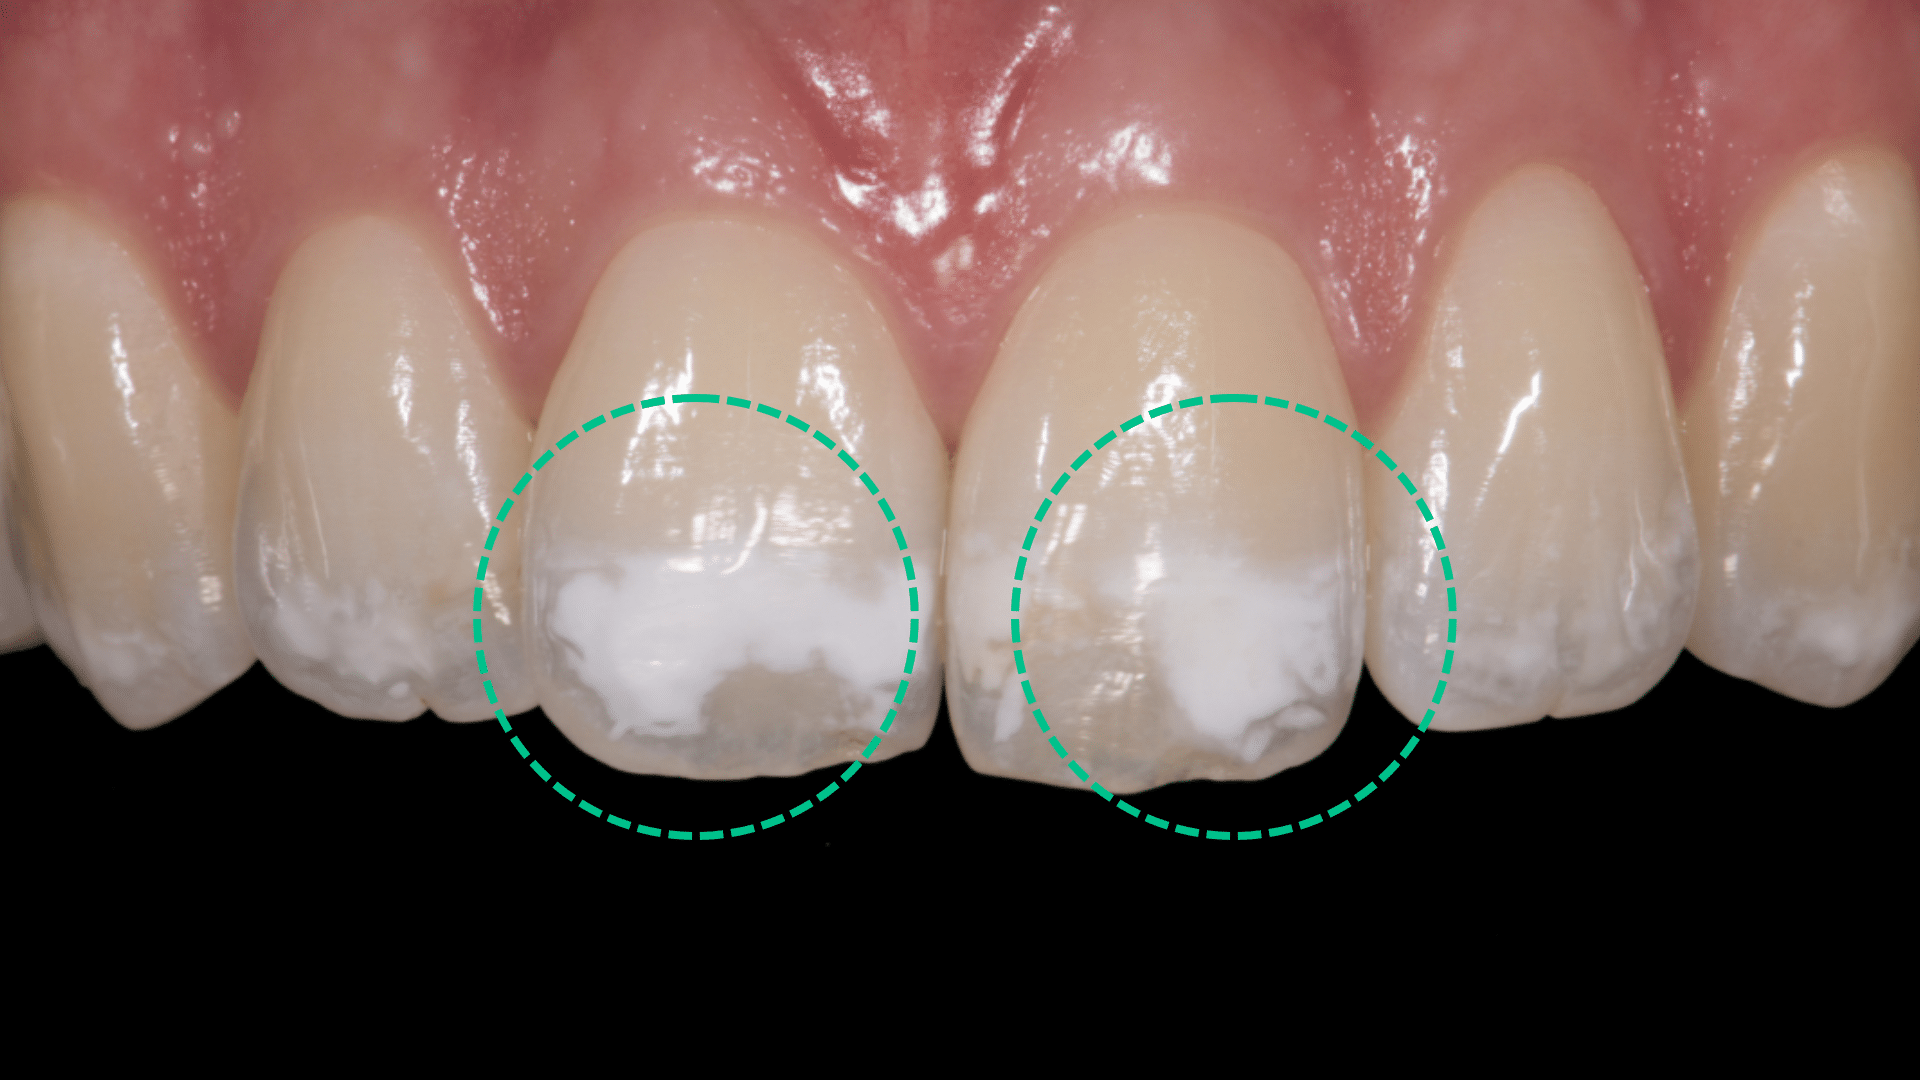

Clinical Definition and Appearance

White spots on teeth are small, lighter patches on your teeth. They show up when the enamel starts to break down. This can happen due to bad dental care, too much fluoride, or enamel hypoplasia.

These spots can show up on any tooth surface. They might be more visible on your front teeth.